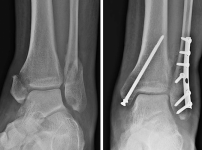

발목골절 양측 복숭아뼈 골절 치료, 기능적 회복이 최우선입니다

1. 발목골절 발생 시 수술 여부를 결정하는 의학적 기준안녕하세요. 환자분들의 소중한 발걸음을 지키는 강동구 서울건우정형외과 최홍준 원장입니다. 일상생활이나 스포츠 활동 중 예기치…